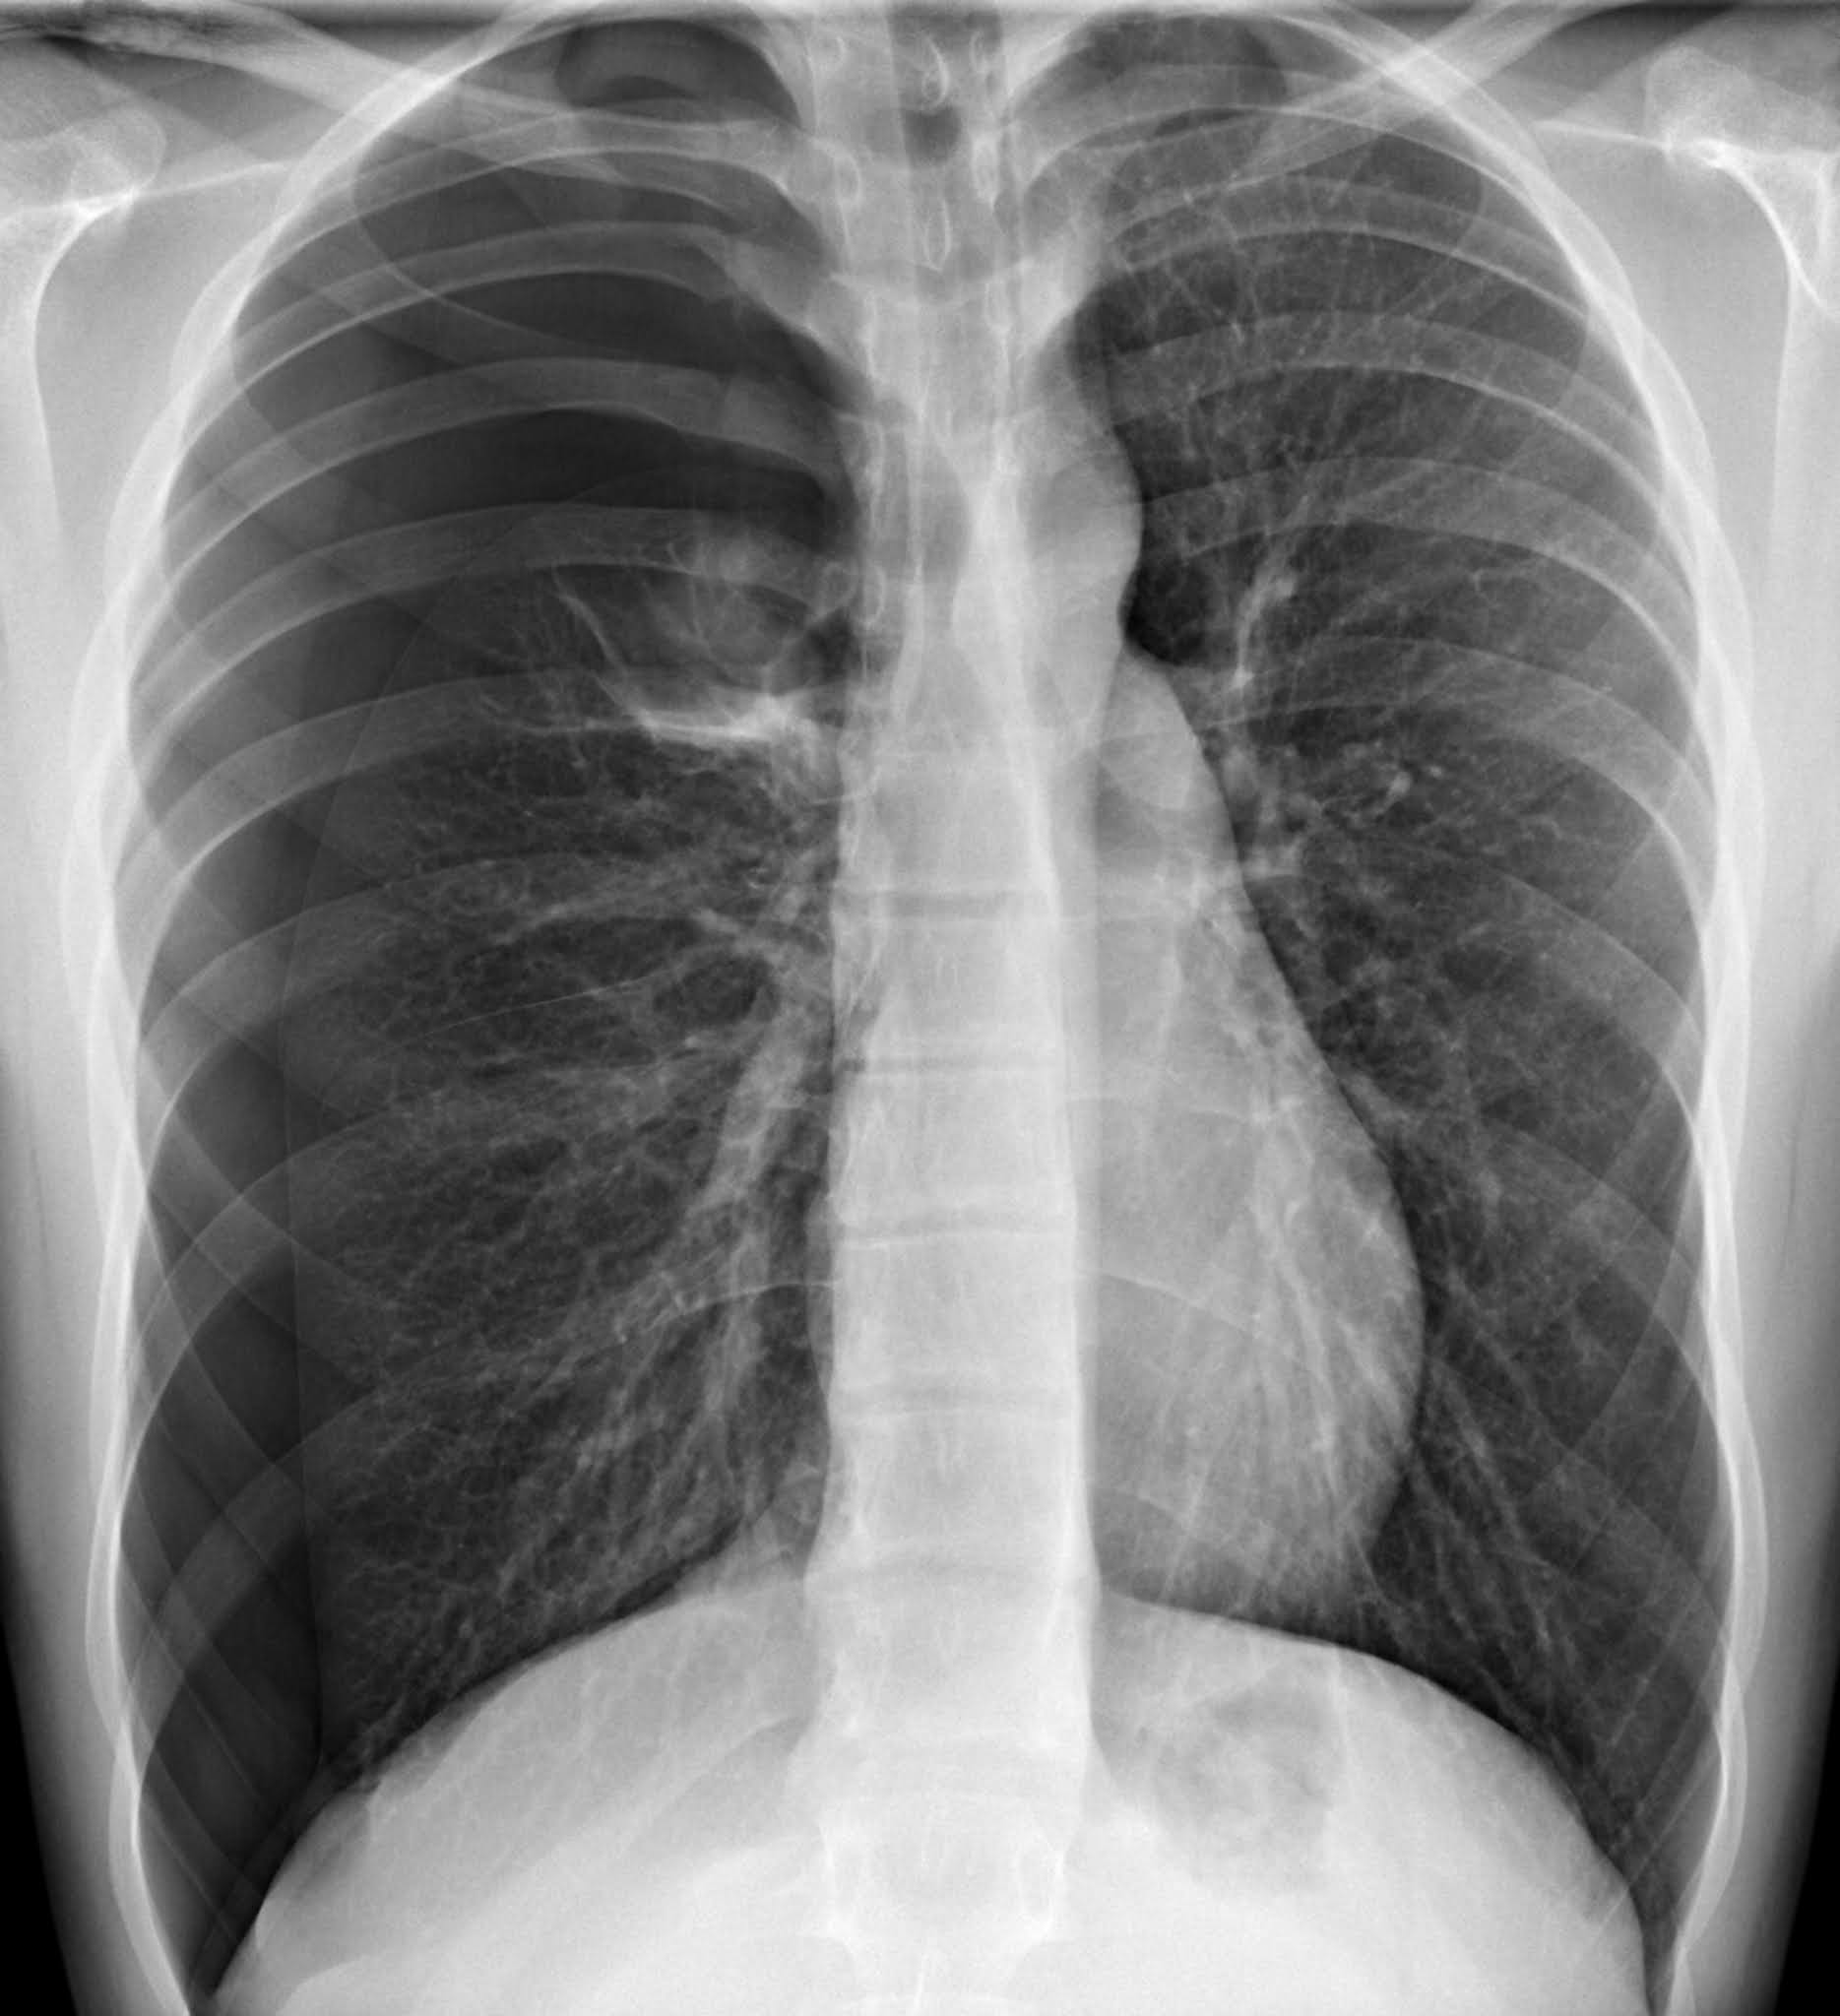

Radiografía de un derrame pleural.

Exámenes complementarios: Radiografía de tórax postero-anterior y lateral, que si es negativa o dudosa pedir radiografía de tórax en decúbito lateral, que si también es negativa o dudosa se pide ecografía pleural o, menos útil, la TAC. En una radiografía encontramos opacidad que borra el contorno diafragmático y tiene una concavidad superior. Si el derrame es >1,500 ml hay desplazamiento mediastínico al lado opuesto; cuando el derrame es <200 ml (pequeño) hay obliteración del seno costofrénico posterior en una RX lateral. En la RX en decúbito lateral vemos desplazamiento de líquido hacia la zona declive y aclaramiento de la base. La ecografía pleural permite detectar derrames de escasa cantidad (10ml); TAC torácica para distinguir lesiones parenquimatosas y pleurales.